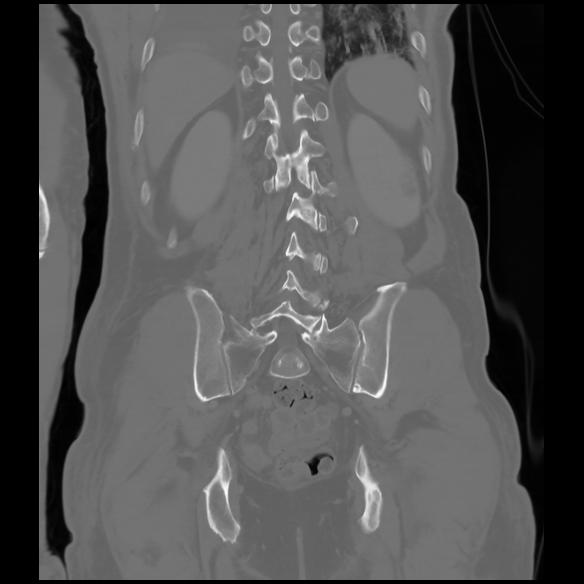

6 CUERPO,CE,Coronal,3.000,CUERPO,Coronal,